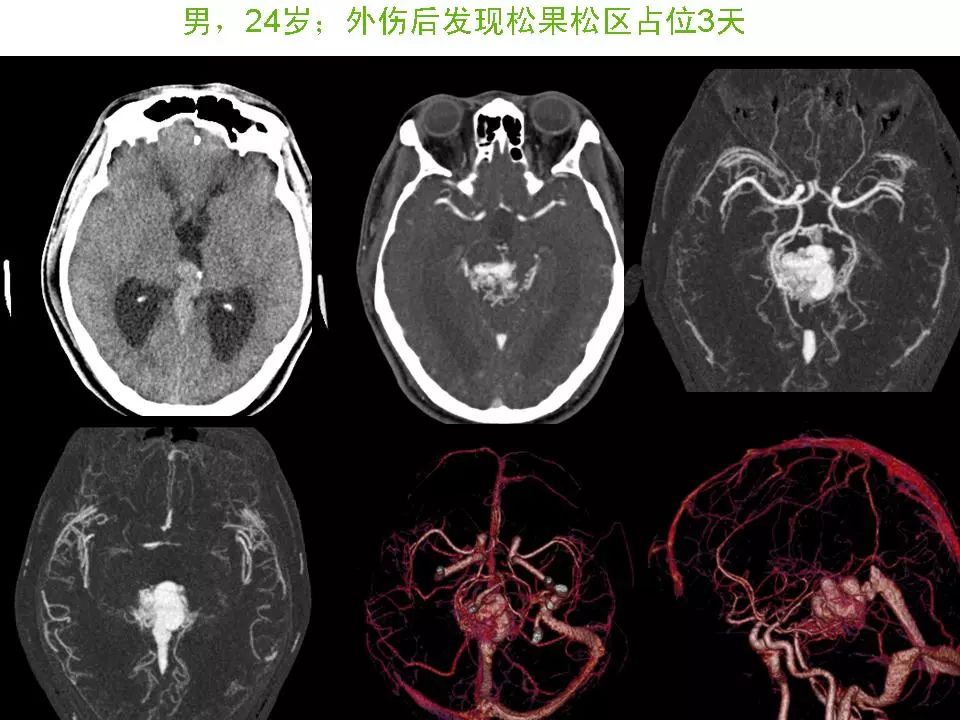

脑血管畸形影像学诊断

图片尺寸931x498

脑血管畸形的影像诊断 | 影像天地

图片尺寸960x720

内血管畸形者做影像学检查协诊 增强(mri swi)

图片尺寸3415x1919

脑血管畸形

图片尺寸1536x2048